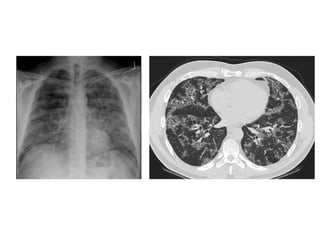

b) Non-specific Interstitial Pneumonia (NSIP) :

Subpleural Ground-glass

-NSIP is less common than UIP

-In non-smokers

-High-resolution CT typically reveals a subpleural and

rather symmetric distribution of lung abnormalities

-The most common manifestation consists of patchy

ground-glass opacities combined with irregular linear or

reticular opacities and scattered micronodules

-In advanced disease, traction bronchiectasis and

consolidation can be seen; however, ground-glass

opacities remain the most obvious high-resolution CT

feature in the typical patient with NSIP

Distribution of NSIP, the distribution is subpleural with no obvious

gradient (red area in a), CT shows ground-glass opacity (gray areas

in c), irregular linear and reticular opacities (blue areas in c),

micronodules (red areas in c), and microcystic honeycombing

(green areas in c)

NSIP in a 60-year-old woman with mild dyspnea and fatigue, high-

resolution CT image of the lower lungs shows bilateral subpleural

ground-glass opacities (arrowhead) and irregular linear opacities

(arrow)

NSIP in a 53-year-old man with mild dyspnea, coronal CT image shows

diffuse lung involvement consisting of peripherally located irregular

linear opacities with ground-glass opacities (arrows), small cystic

lesions are seen (arrowhead)

48-year-old woman with scleroderma, cough, and dyspnea and biopsy-proven

nonspecific interstitial pneumonia, high-resolution CT through lower lungs

shows scattered ground-glass opacities that are relatively symmetric in

distribution, accompanied by bronchiectasis, honeycombing is absent, note

dilated esophagus, finding associated with scleroderma

(a) UIP is characterized by heterogeneous lung abnormalities consisting of

subpleural honeycombing (arrowhead), reticular opacities, and traction

bronchiectasis, (b) NSIP demonstrates homogeneous lung involvement with

predominance of ground-glass opacity combined with sub-pleural linear

opacities and micronodules. The microcysts in NSIP (arrowhead) are much

smaller than the honeycombing in UIP